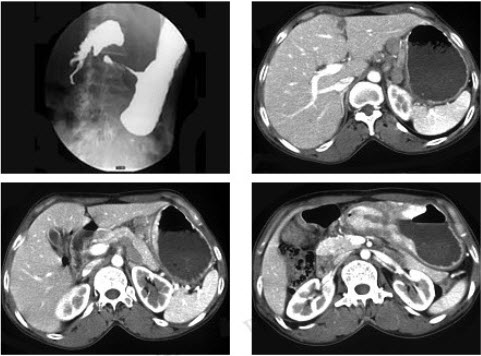

女,56岁,上腹部钝痛、腹胀不适1月余,纳差、消瘦,影像检查如图,最可能的诊断是()

A:胃幽门管溃疡

B:胃腺癌并幽门狭窄

C:胃淋巴瘤

D:胃间质瘤

E:胃恶性间质瘤